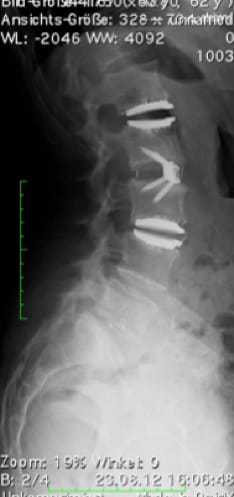

Postoperative status: Complete axial correction of the lumbar spine with two disc prostheses and a PEEK cage. Normal lordosis of the lumbar spine also visible in the lateral view after the operation. (Spine Centre Rischke)

(2) Example of treatment with a viscoelastic disc prosthesis and dynamic fixator in the presence of spondylolisthesis